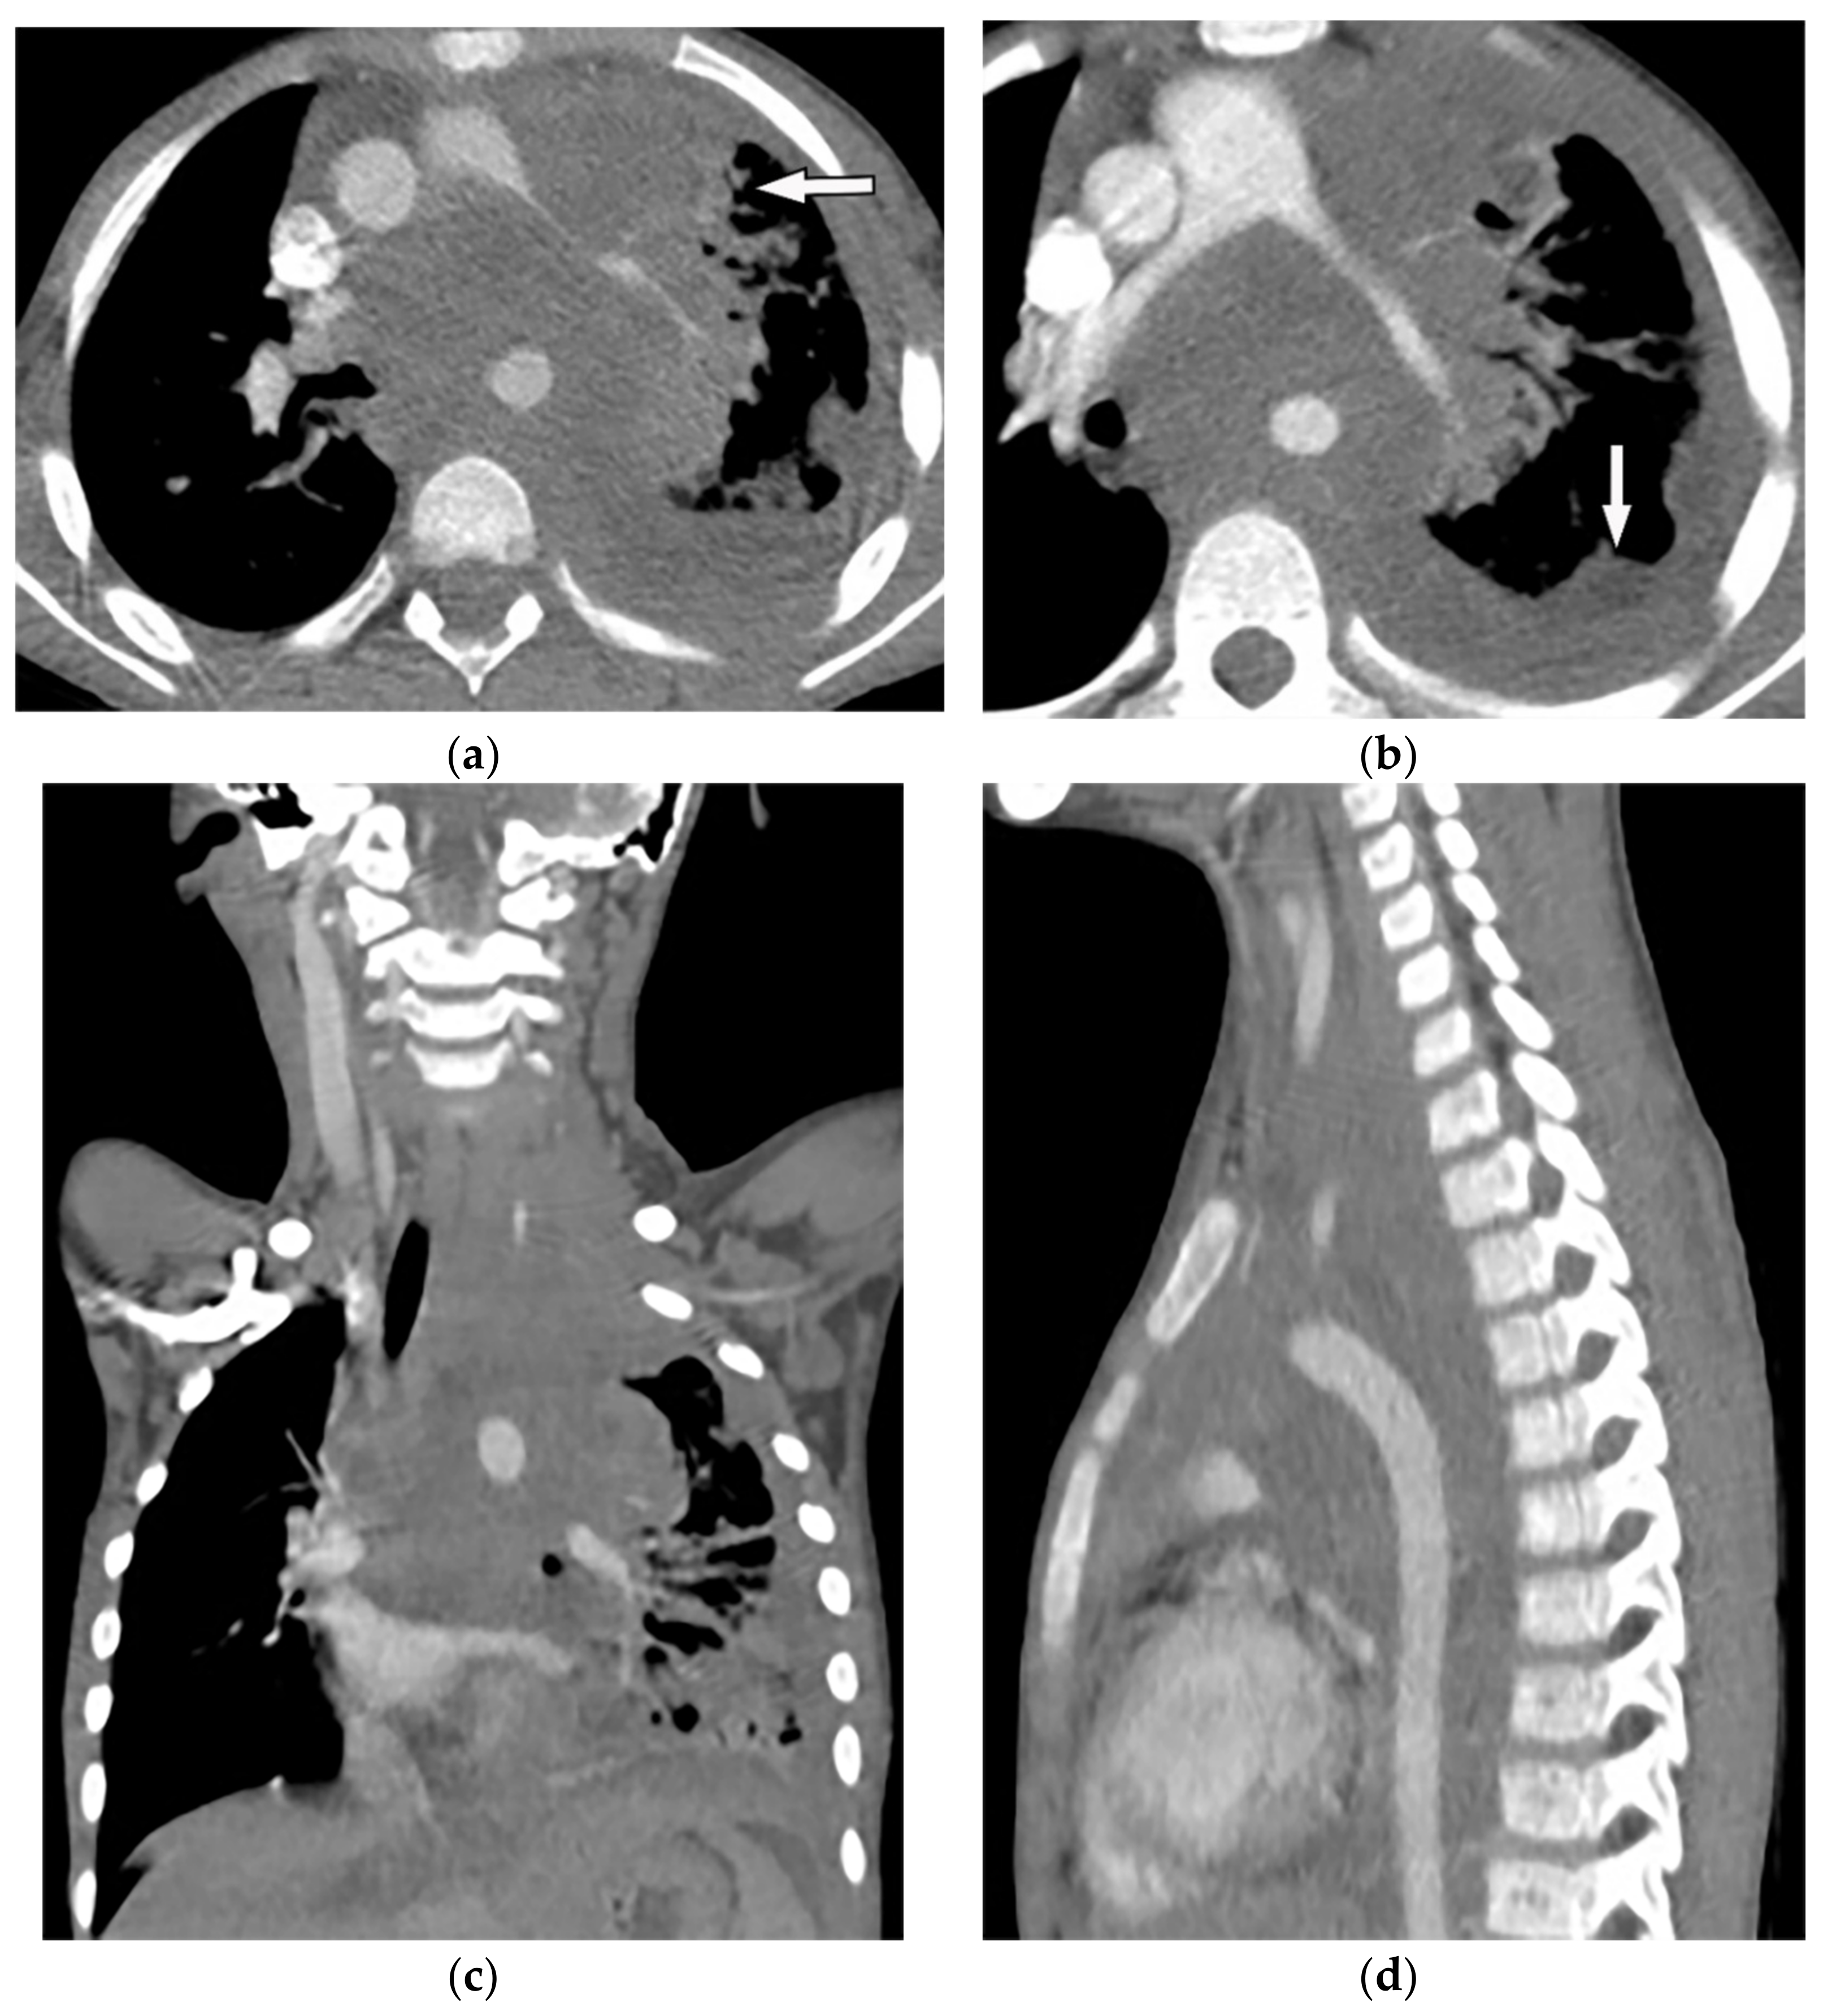

| Empyema necessitance | Connection of pleural collection to extrapleural mass, soft tissue inflammation, rib destruction with periosteal reaction, and fluid collection. | T1W: hypointense effusion and fluid collection T2W: hyperintense effusion, increased thickness of extrapleural fat, and chest wall muscles with hyperintense on T2WFS T1WFS + C: pleural and septal enhancement |